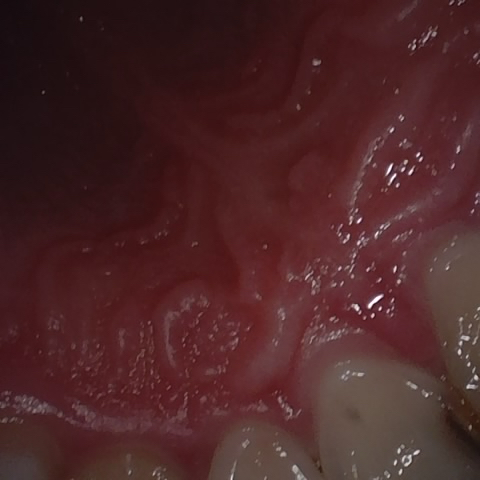

Annotated as "Bad"